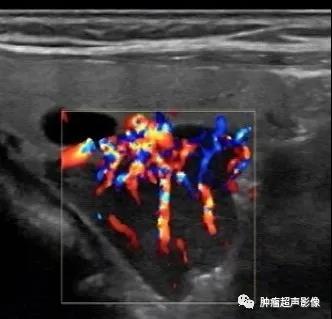

5、血流:一般血流丰富,血流表现为极性特点,由一端进入后呈分支状,或绕行半圈进入,有些血流从上半部分垂直进入(瀑布样),一般无甲状腺腺瘤的环形血流。

病理证实的甲状旁腺腺瘤:位于甲状腺背侧,完整的包膜,呈低回声,血流丰富呈瀑布样,符合典型的甲状旁腺腺瘤。